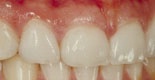

Fyra skalfasader före och efter behandling. De två understa bilderna visar en gipsmodell av patienten, i vy från gommen och tuggytorna på framtänderna. Till höger kan du se de tunna keramiska fasaderna.